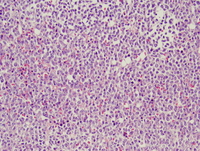

Marrow Biopsy

The trephine core is hypercellular with most of the cellularity composed of immature cells.